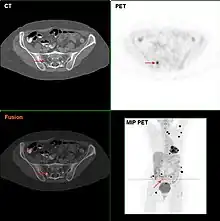

Metastatic melanomas can be detected by X-rays, CT scans, MRIs, PET and PET/CTs, ultrasound, LDH testing and photoacoustic detection.[85] However, there is lack of evidence in the accuracy of staging of people with melanoma with various imaging methods.[86]